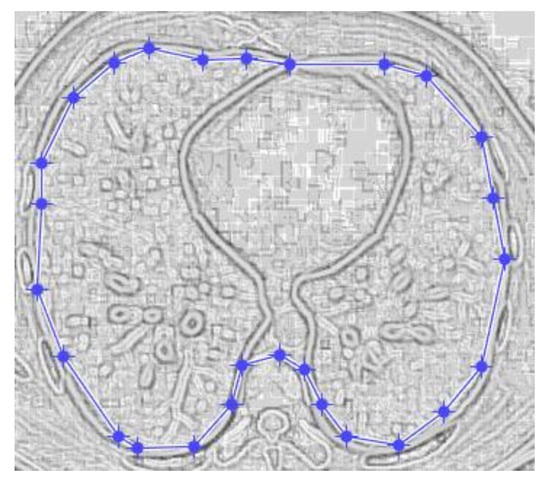

Figure 9 and Figure 10 show the original CT lung image, respectively, and the defined mask for the COVID-19 lung CT image, framed in a blue border in Figure 10.

Figure 10 presents the applied mask across the COVID-19 lung CT image, framed in a blue colour border.

Figure 10. Mask applied for COVID-19 lung image.